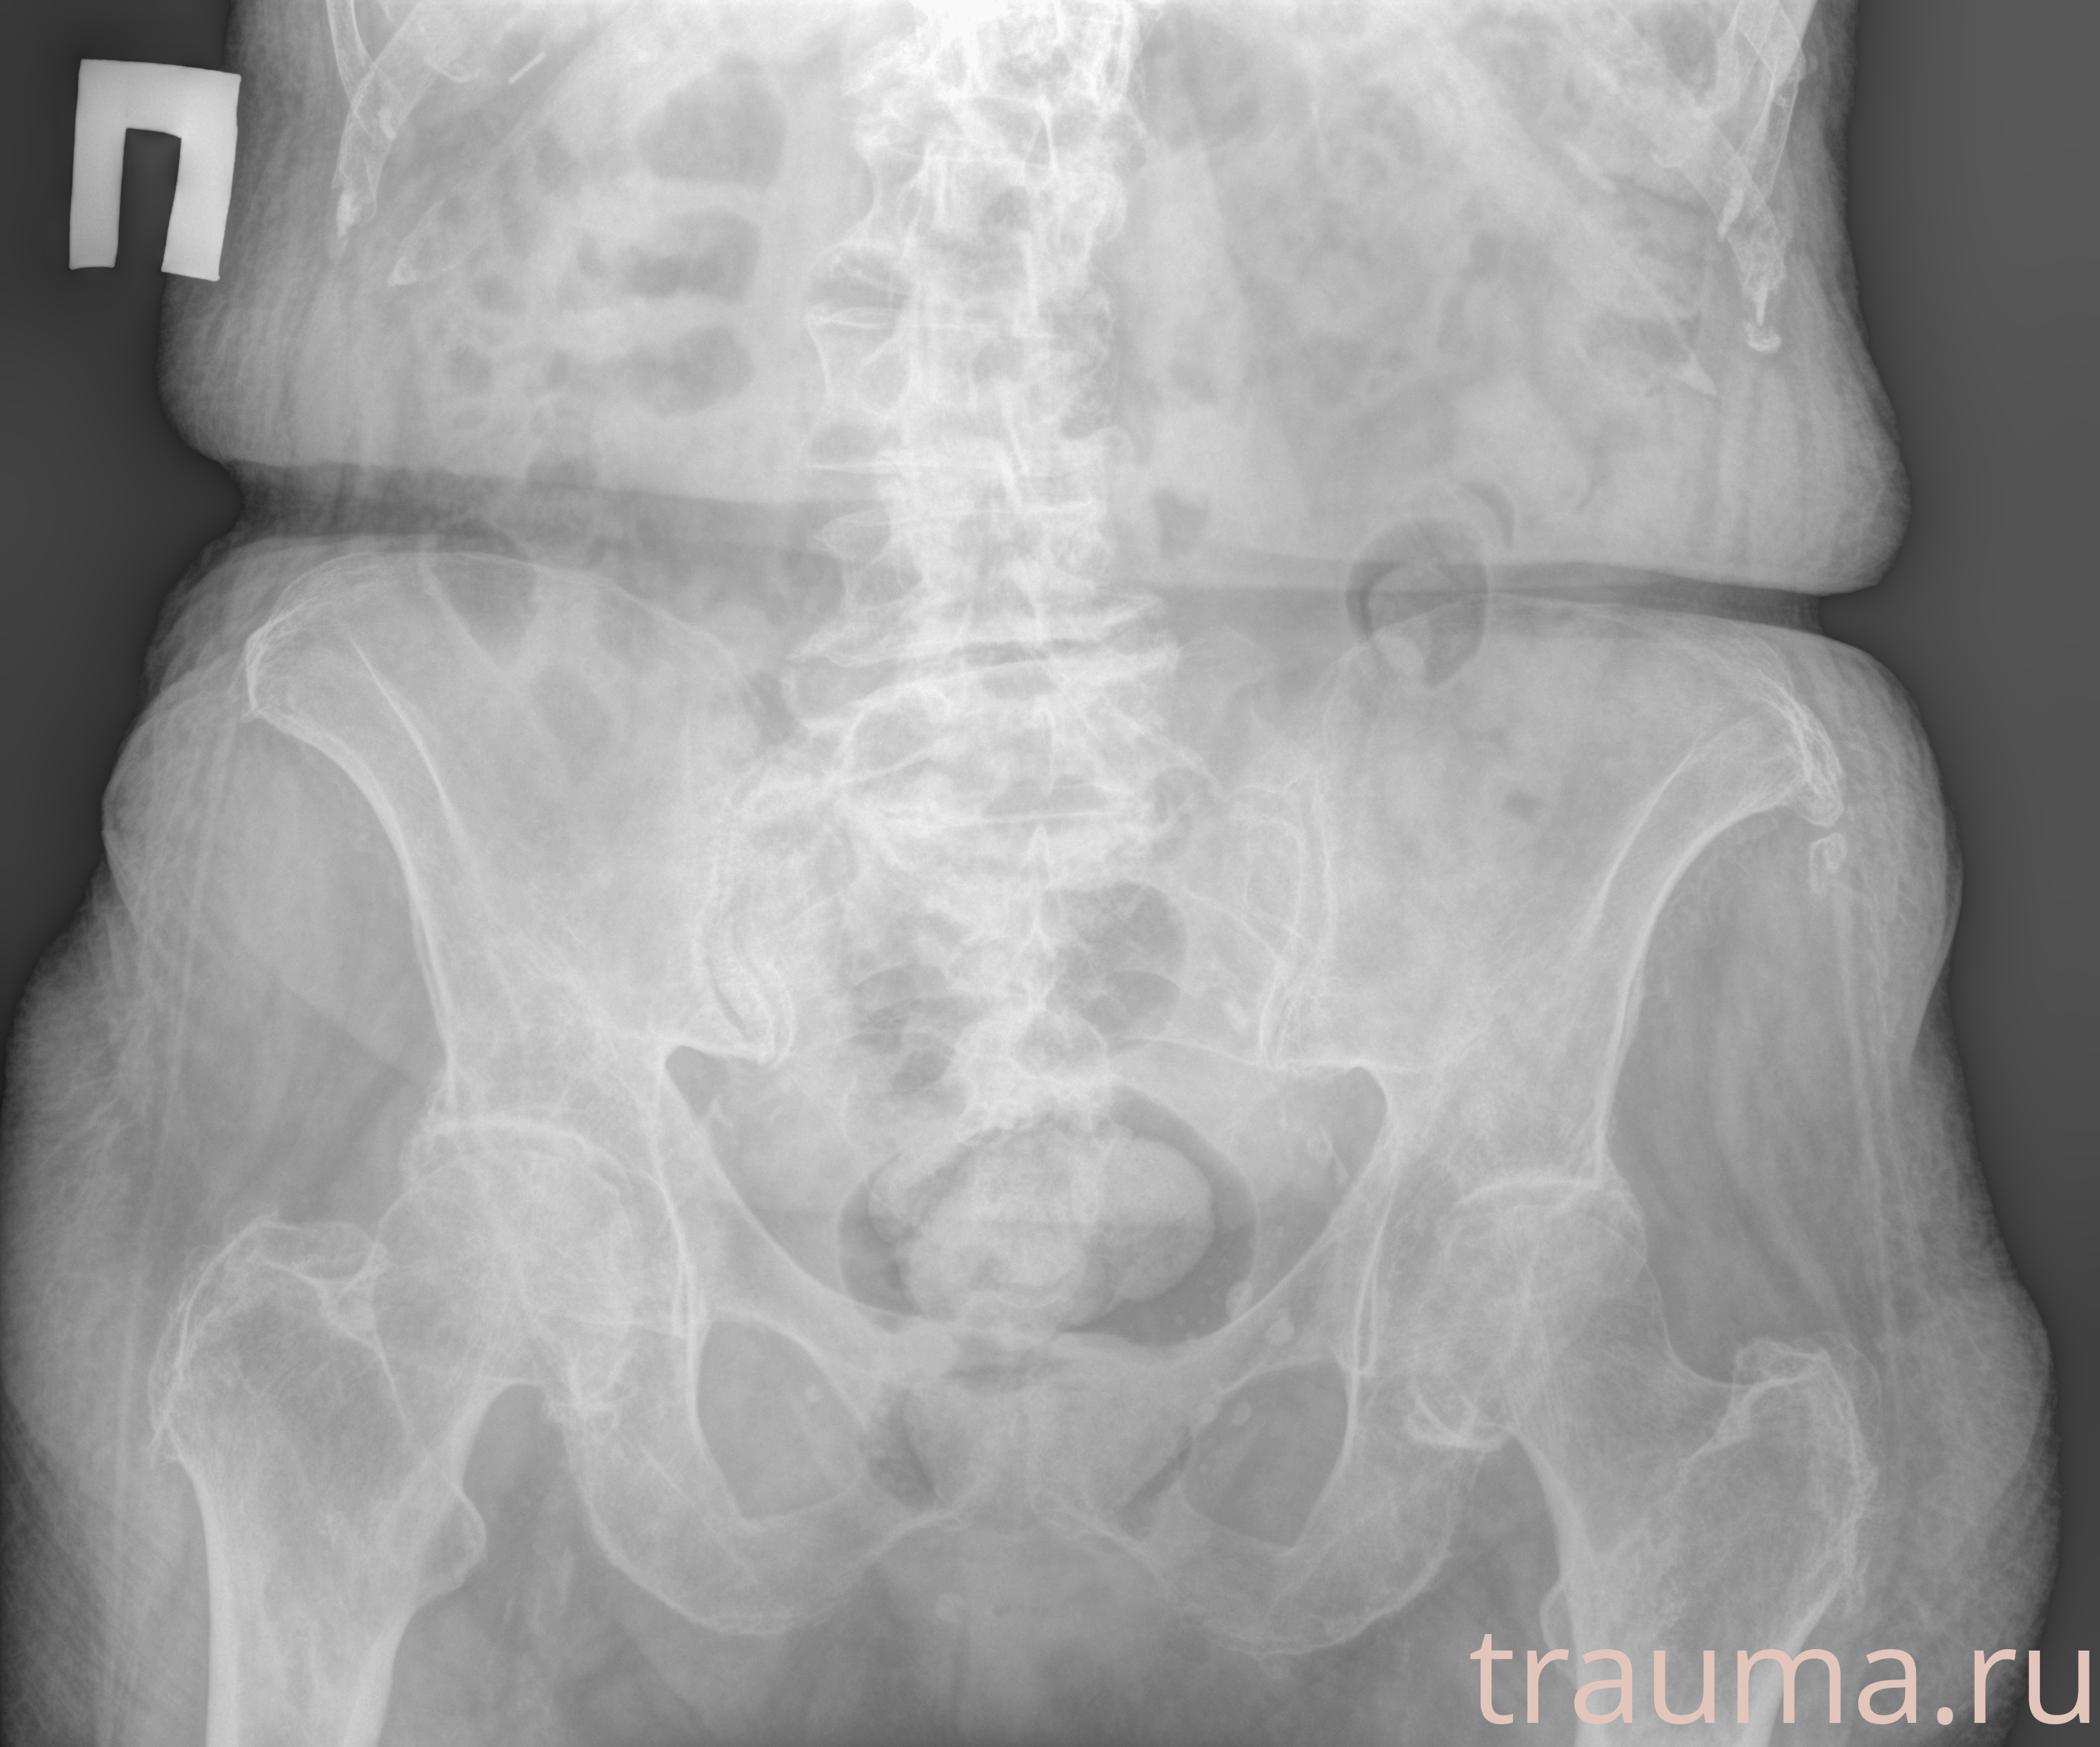

Рентген на дому: по вашему адресу приезжает врач-рентгенолог, травматолог-ортопед с мобильным рентгеновским аппаратом, проводит диагностику травмы или заболевания, делает необходимые рентгенограммы, дает рекомендации по дальнейшему лечению. Получить качественные снимки в домашних условиях возможно благодаря уникальной методике, разработанной МосРентген Центром для института  Склифосовского

при переломе шейки бедра и пневмонии от компании МосРентген Центр - партнера Института имени Склифосовского